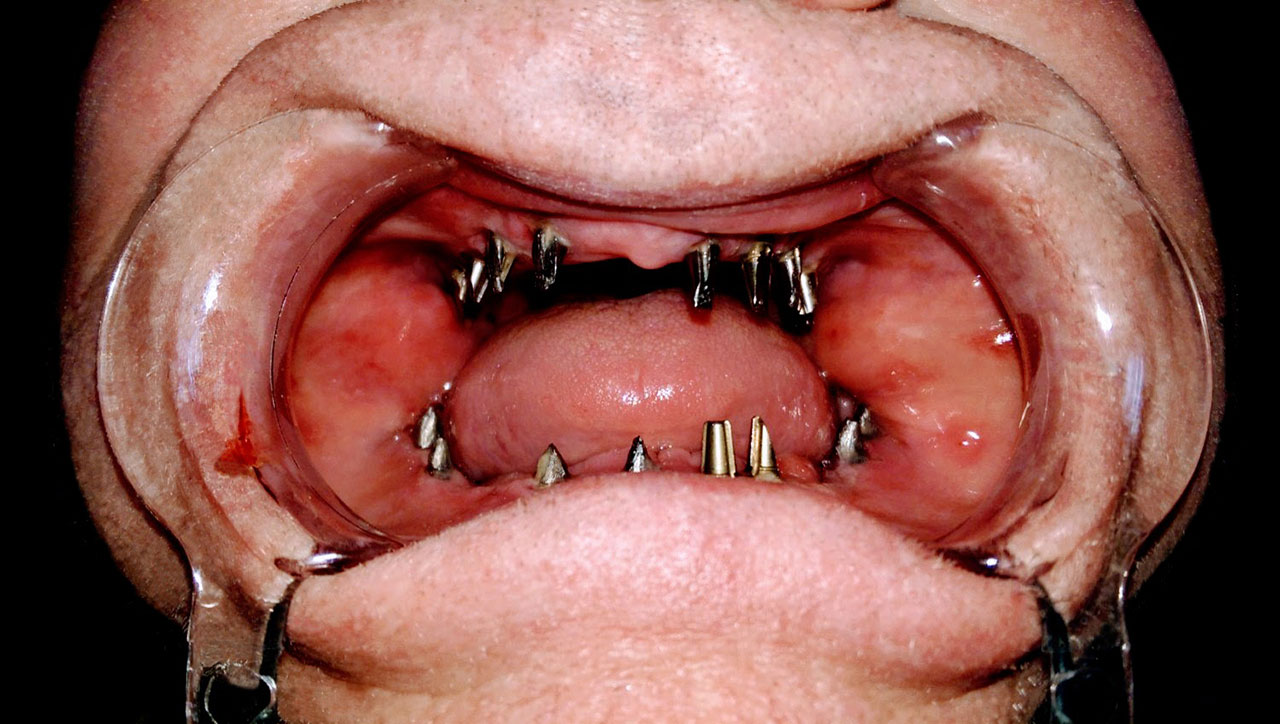

Sikerét mindenekelőtt a gyorsaságának köszönheti, hiszen a mai rohanó világban kinek van ideje, kedve fogatlanul otthon ülni heteket, hónapokat a fogpótlásra várva? Az Ihde implantációs eljárás során a páciens azonnal, de legkésőbb 72 óra múlva egy rögzített (tehát nem mozgó, nem kivehető) pótlással hagyja el a rendelőt. Ez az egyedülállóan gyors eljárás annak köszönhető, hogy azonnal tudunk implantálni szinte bárhova, akár foghúzás után is, továbbá a művelet nem jár nagy feltárásokkal, nincs szükség csontbeültetésre, így a gyógyulás folyamata is nagyon gyors és a beültetés technikájának köszönhetően maximum 72 óra múlva a korona is feltehető. Tehát ennyi idő alatt foga lesz a betegnek és az implantátum azonnal terhelhetővé is válik.

Az eljárás mellett szól az is, hogy nagyon biztonságos. A cég adatai alapján a beültetett implantátumok 98.2%-a sikeres. Az azonnali terhelésű implantátumokkal rögtön, akár foghúzás után is szinte bárhová lehet implantálni, bárkinek, legyen szó cukorbeteg, dohányos, vagy akár csontritkulásban szenvedő páciensről. Ennek köszönhető, hogy a betegek 99%-ánál alkalmazható a módszer.